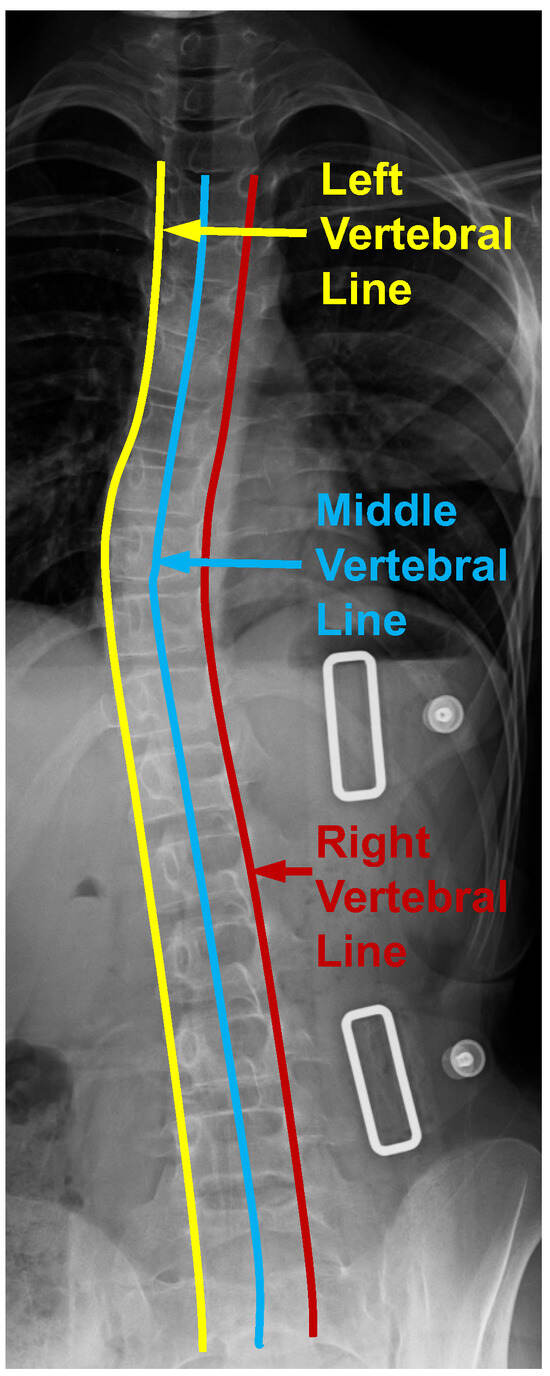

Figure 3.

Four vertebral lines on the cervical spine image, including the anterior, posterior, spino-laminar, and posterior spinous lines.

From Figure 1, the vertebral line interpolation pathway in the rectangular box on the right shows how this proposed scheme works in the whole framework. Similar to the center point interval estimator pathway and the adjacent vertebra interval estimator pathway, the vertebral line interpolation pathway works as an auxiliary task in the training process. It provides additional information for better model supervision. As shown in Figure 4, we extract three vertebral lines, which include the left vertebral line, the right vertebral line, and the middle vertebral line. For the left vertebral line, we first extract all the (, ) and (, ) corner points. After that, we construct a b-spline curve so that all these 34 corner points are lying on this curve and then take 100 points equidistantly along this curve as the optimized ground truth. As for the right vertebral line, we first extract all the (, ) and (, ) corner points. The following process is the same as obtaining the left vertebral line. For the center vertebral line interpolation, first, by taking the average value of the four annotated landmarks of each vertebra, the coordinates of all center points can be obtained, which can be seen from Figure 2a. Since these 100 points from the above-mentioned three vertebral lines are very dense, we can use them as a line that can describe the overall morphology of the patient’s spine. It should be noted that the center points are obtained from four corner points representing the whole vertebra. The experimental results show that there is almost no performance difference using only the middle vertebra line. Therefore, we only used the middle vertebral line to decrease the number of parameters during the experiment. By providing extra information on the lines to the model, it is possible to enhance the accuracy of recognizing landmarks through the joint learning of points and lines. The L1 loss is used to optimize the parameters in this vertebral line interpolation pathway. The overall loss of this pathway contains three components: the left vertebral line loss, the middle vertebral line loss, and the right vertebral line loss. This is shown in Equation (3), where the subscripts l, m, and r indicate left, middle, and right, respectively.

Figure 4.

Three vertebral lines on the spinal anterior–posterior X-ray images, including the left, middle, and right vertebral lines.